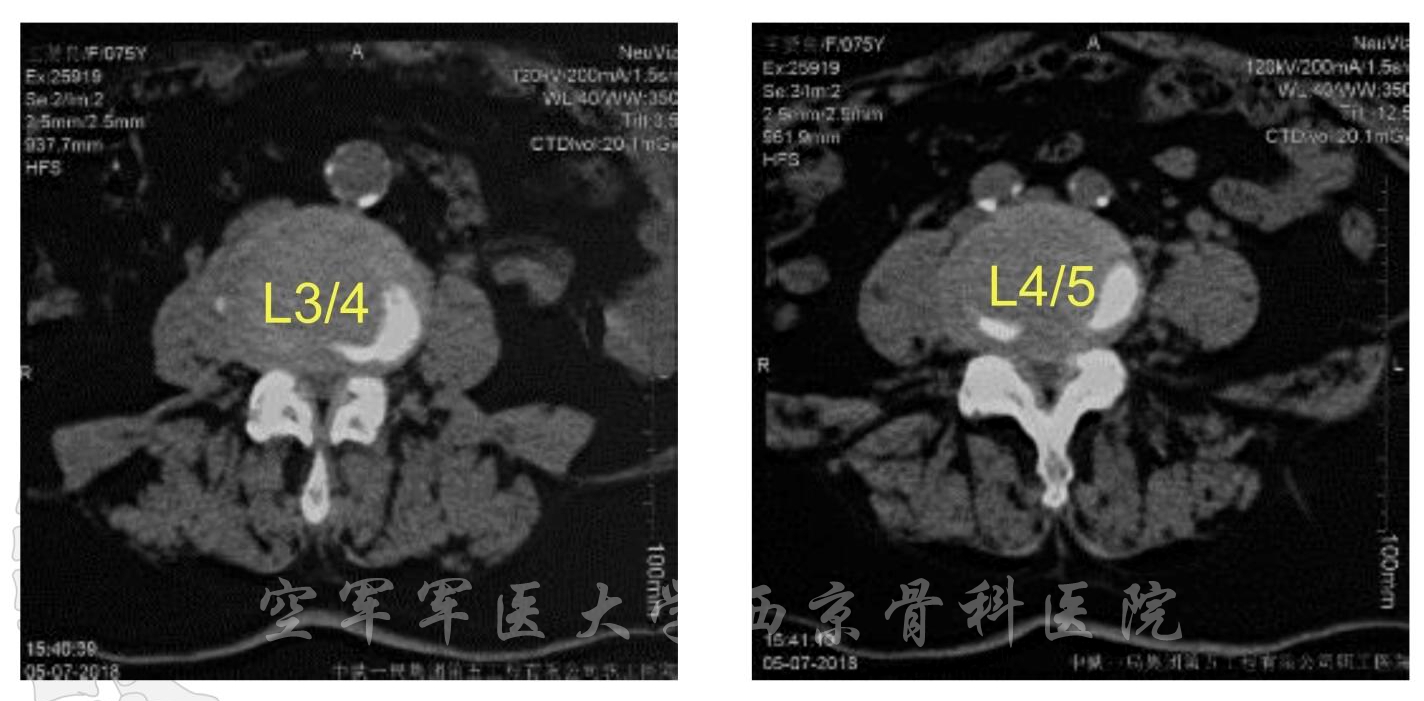

术前CT